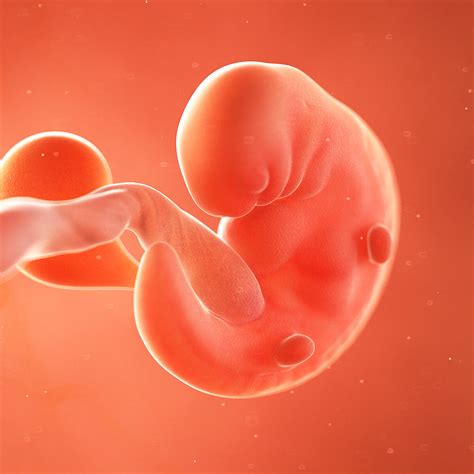

At 4 weeks, babies undergo remarkable physical changes. Their bodies are adapting to life outside the womb, and their senses are becoming more acute. Here are some key physical developments to look out for:

• Sensory Development: Babies' senses are becoming more sensitive. They can see objects more clearly, especially high-contrast images, and their hearing is improving. They may also start to recognize familiar voices and sounds.